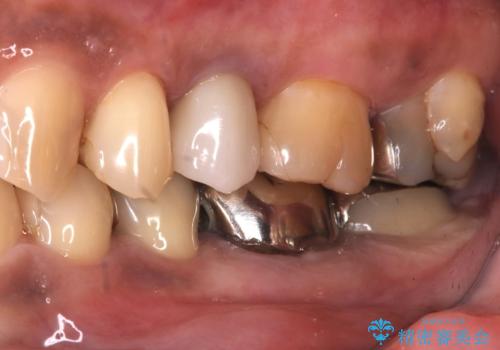

- 主訴:銀の詰め物が何本か入っているので白くしていきたい

保険適用のメタルインレーのやり替え希望だったため、審美性・適合性の良いセラミックインレーでのやり替えとなりました。

メタルインレーを除去したところ、二次カリエスうを確認したため除去・CR裏層の後、形成・印象しています。